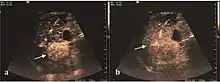

Hepatic hemangioma (CEUS). Progression of CA from the periphery toward the center of the lesion is evidenced by examination at various time intervals (a – arterial phase; b – late phase).

It is the most common liver tumor with a prevalence of 0.4 – 7.4%. It is generally asymptomatic but also can be associated with pain complaints or cytopenia and/or anemia when it is very bulky. It is unique or paucilocular. It can be associated with other types of benign liver tumors. Characteristic 2D ultrasound appearance is that of a very well defined lesion, with sizes of 2–3 cm or less, showing increased echogenity and, when located in contact with the diaphragm, a "mirror image" phenomenon can be seen. When palpating the liver with the transducer the hemangioma is compressible sending reverberations backwards. Doppler exploration reveals no circulatory signal due to very slow flow speed. CEUS investigation has real diagnosis value due to the typical behavior of progressive CA enhancement of the tumor from the periphery towards the center. The enhancement is slow, during several minutes, depending on the size of hemangioma and on the presence (or absence) of internal thrombosis. During late (sinusoidal) phase, if totally "filled" with CA, hemangioma appears isoechoic to the liver. Deviations from the above described behavior can occur in arterialized hemangiomas or those containing arterio-venous shunts. In these cases, differentiation from a malignant tumor is difficult and requires other imaging procedures, follow up and measurements of the tumor at short time intervals.[4]